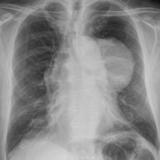

Thymic carcinoma PA

Date: 08/15/2012

Views: 6255